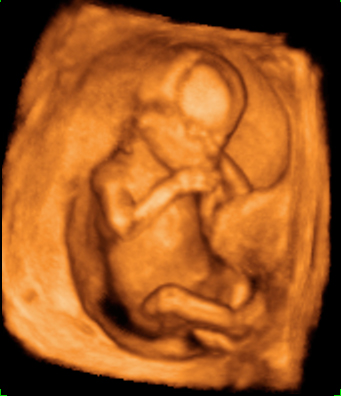

Ecografía semana 12 de embarazo gemelar

Los bebés tiene la cabeza en direcciones opuestas

Ecografía 4D de gemelos de 12 semanas "contrapeados": Cada uno de los bebés está con la cabeza en una dirección, tal y como podemos visualizar en el ultrasonido. Uno de los gemelos se mueve al final de las imágenes de la ecografía mientras su hermano descansa.

Ecografía en 4D de gemelos de 12 semanas "contrapeados"

Cada gemelo está con la cabeza en una dirección, tal y como se aprecia en esta ecografía en 4D. Los dos fetos "contrapeados" tienen bolsas y placentas independientes. Destaca el movimiento del gemelo que aparece en la parte superior de la imagen: pareciera que se "arranca" a bailar al final del vídeo, mientras que su hermano permanece más tranquilo en su bolsa.